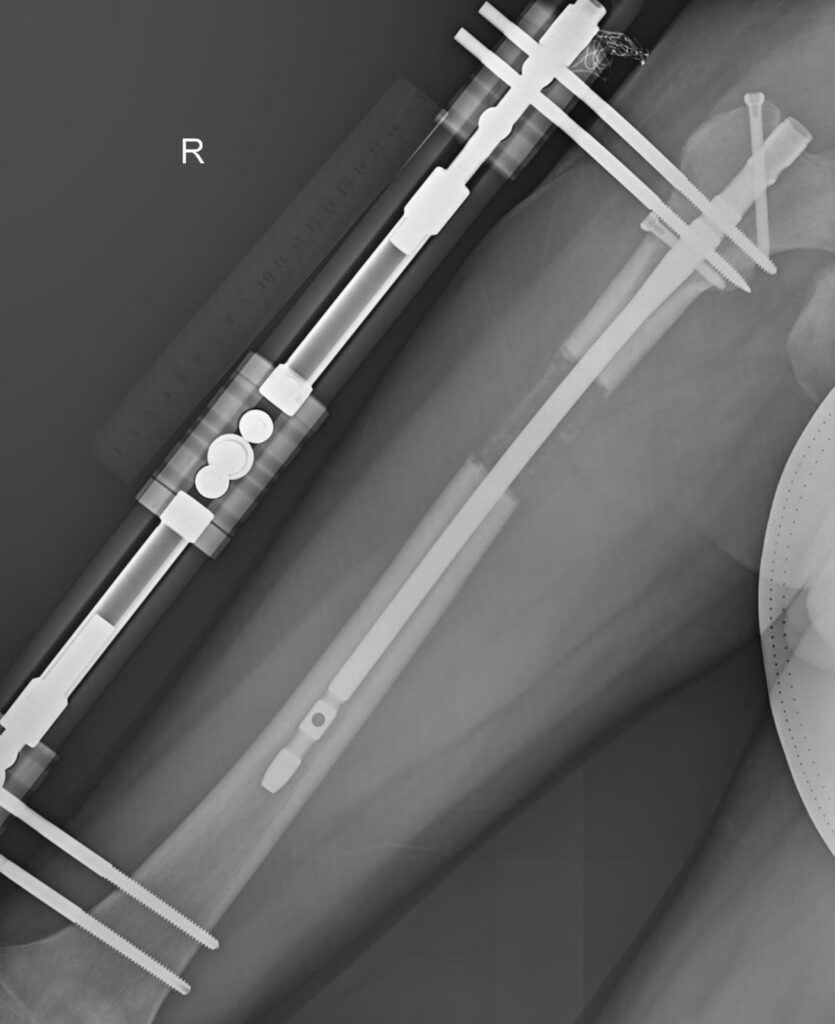

This image shows the femur lengthening procedure using the LON method. Patients can achieve up to 10 cm (4 inches) of height increase in one procedure with this technique. It is a popular choice for patients looking for maximum height gain in a single treatment.

The LON method involves placing an internal nail inside the bone, which remains connected to an external fixator during the distraction phase (lengthening process). Once the desired length is achieved, the external fixator is removed through a minor surgical procedure, while the internal nails continue to support the bone until full consolidation. The LON method is weight-bearing, enabling patients to begin walking with assistance as early as 2-3 weeks after surgery. This early mobility helps patients maintain independence and meet their daily needs throughout the lengthening phase.

The LON (Lengthening Over Nails) method is a widely used and cost-effective approach for limb lengthening. By combining intramedullary nails with external fixators, this technique provides an ideal balance of affordability, comfort, and effectiveness. This method allows patients to safely increase their leg length in a relatively short period while minimizing risks and discomfort with proper care.